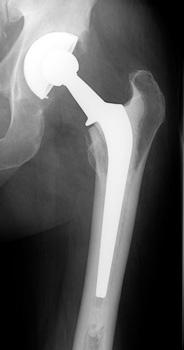

Total Hip Arthroplasty

• Used in patients with arthritic conditions that involve the acetabulum and the femoral head

• Types

• Non cemented

• Porous coated

• Press fit

• Hybrid (only femoral component cemented)

• Cemented

Cemented